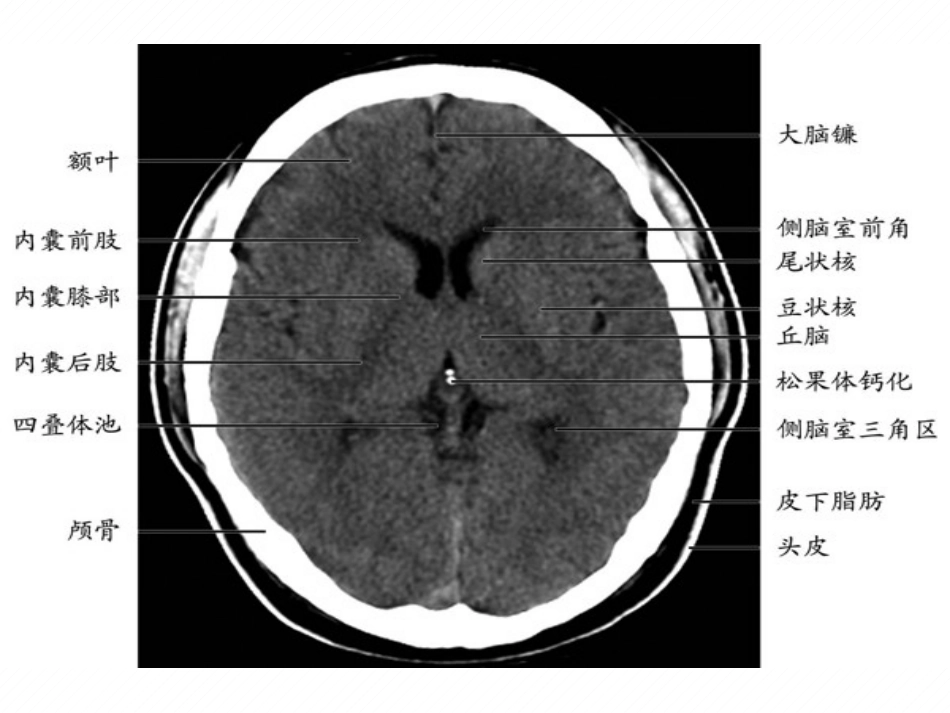

基底节区对称性病变病因和影像学特征本文非原创(参考了几个PPT)基底节又叫基底核,是埋藏在两侧大脑半球深部的一些灰质团块,是组成锥体外系的主要结构。它主要包括尾状核、豆状核(壳核和苍白球)、屏状核以及杏仁复合体。基底节区,是影像学名词。包括:基底节及其周围白质、内囊。为一不太明确的区域。病因一.中毒性疾病:1.CO中毒2.变质甘蔗中毒3.氰化钾中毒:4.海洛因海绵状白质脑病二.感染性疾病:1.病毒性脑炎:2.慢病毒感染:如CJD,NVCJD3.AIDS三.营养代谢性疾病:1.肝豆状核变性:铜的异常沉积2.FAHR病以及甲旁减等:钙的异常沉积3.肝性脑病:锰的异常沉积4.Leigh综合征5.维生素B1缺乏症四.缺氧性脑病:五.脑血管病:双侧对称性出血或梗死六.变性疾病:结节性硬化、Huntington病,CO中毒性迟发性脑病影像特点:①CT可表现正常,重度患者的CT可表现为脑水肿,一侧或双基底核区缺血性低密度改变。②MRI表现为脑室周围白质和双侧半卵圆中心对称性融合病灶在T1加权相呈低信号而T2加权相高信号,病灶可波及皮质下内囊、外囊,基底核可有缺血坏死表现病情严重时,在T1加权相上可见到假性分层坏死。猫眼征—CO中毒性迟发性脑病CJD(克雅氏病)克雅氏病是一种罕见的可传播的脑病,由朊病毒引起的人和动物中枢神经系统的退行性脑病。表现进行性痴呆,肌阵挛、视觉或小脑障碍、锥体/锥体外系功能异常。Creutzfeldt-JakobDisease克-雅氏病图A丘脑为正常的等信号或稍低信号,FLAIR表现为丘脑呈对称高信号及曲棍球棒改变。.影像改变:双侧尾状核、豆状核、丘脑弥散受限,双侧丘脑呈“曲棍球征”改变肝豆状核变性肝豆状核变性,又称威尔逊氏病(Wilson)的铜代谢障碍疾病。是一种常染色体隐性遗传性铜代谢障碍所致的肝硬化和以基底节为主的脑部变性疾病。颅脑影像学检查,表现为双侧对称性病变,且豆状核、尾状核头部的大部分受累,而丘脑则为局部受累。脑干病灶则以桥脑和中脑病变为主,少见小脑病灶。因而,对称性基底节异常信号同时伴有脑干病灶是Wilson的影像特征之一。肝豆状核变性CT上表现为脑萎缩及双侧豆状核对称性低密度改变,低密度呈条状或新月状肝豆状核变性基底节区、白质、丘脑和脑干T1相低信号。T2相质子加权、FLAIR上呈高信号。甲状旁腺功能减退甲状旁腺功能低下时,甲状旁腺素分泌不足可以引起钙磷代谢紊乱,血钙降低,钙质在脑内异常沉积,最先见于基底核,其次为丘脑和小脑齿状核。基底核、丘脑、小脑齿状核及脑实质内多发性对称性钙化,齿状核、丘脑钙化呈“八”字形,尾状核头部钙化呈倒“八”字形,脑实质钙化形态与脑回的形态基本一致。Fahr病(特发性基底节钙化症,或特发性家族性脑血管亚铁钙沉着症)特发性基底节钙化症:以双侧基底节、小脑齿状核、双侧丘脑及皮-髓质交界区中枢对称性钙质沉着为主要病理学特征的疾病。多为家族遗传性,表现为常染色体显性或隐性遗传.获得性肝性脑部变性AHCDAHCD是慢性肝病引起的一种不可逆的锥体外系综合征。临床上,主要表现为异常运动,构音障碍,意向震颤,共济失调及智力受损。MRI的特征性表现为两侧苍白球、中脑红核周围、垂体前叶等部位出现的T1WI高信号,而T2WI无相应的异常信号,可能是由于门脉高压、门腔静脉分流的存在,门脉血液不经过肝脏解毒直接进入体循环,使得一些顺磁性物质在上述部位沉积海洛因海绵状白质脑病症状:瘫痪、麻木、言语不清、走路不稳等许多症状.死亡率达23%。MRI表现为脑白质的广泛对称性损害,主要累计小脑白质/内囊后肢及膝部/胼胝体压部及体部/顶枕叶白质和脑室周围白质,也可以累及脑干及额颞叶白质;其MRI表现以小脑中线两旁的对称性类圆性或蝴蝶样病灶最具特点,内囊后肢及顶枕叶白质大多有累及而内囊前肢不受累是另一特点。Wernicke脑病Wernicke是慢性酒精中毒常见的由于维生素B1缺乏引起的中枢神经系统的代谢性疾病。以精神障碍、眼肌麻痹和共济失调性步态为主要症状。由于Wernicke典型的3组症状并不常见,其中尤以眼肌症状最为重要。如病人仅出现精神异常,特别以记忆能力缺失为特点时,称为kosakoff综合征。诊断:Wernicke患者的双侧丘脑和脑干有对称性病变,其典型的改变为第三脑室和...